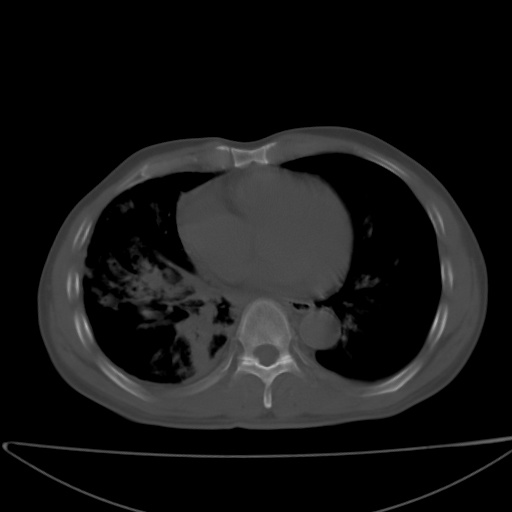

以下是引用jsgdoctor在2008-11-6 22:12:00的发言:[br]右主支气管壁明显增厚,管腔狭窄.考虑为右侧中央型肺癌伴阻塞性炎症\\肺脓肿.

以下是引用zjzjr在2008-11-6 20:25:00的发言:[br]中心型肺ca,合并阻塞性肺炎

以下是引用zsl6918在2008-11-6 19:43:00的发言:[br]右侧中心性肺癌(鳞癌)